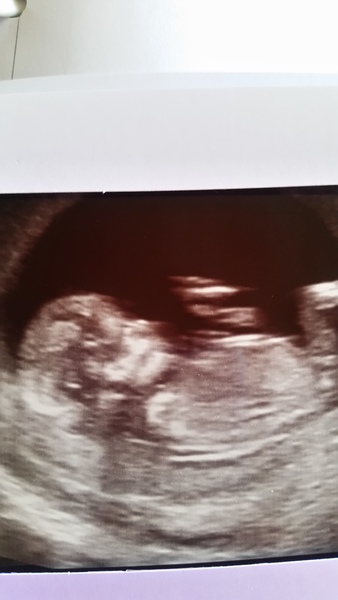

Anyone see the nasal bone on this.. 12 weeks 6 days